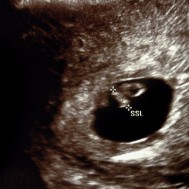

Baby: Week 7

At week 7 all essential body parts are present and accounted for!

All essential body parts are present and accounted for. Your ankles have formed, your arms are long and bend at the elbows. With basic physiology in place, rapid growth and weight gain are the next steps![1]

You are intricately detailed, but still so tiny, only about 3/4 inch (20 millimeters) long.[2]